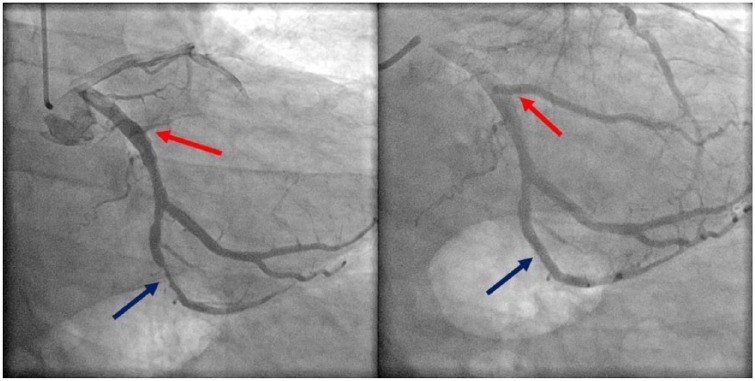

პაციენტი ჰოსპიტალში გადაიყვანეს დაკვირვებისთვის იმის გათვალისწინებით, რომ მას დატვირთული კორონარული არტერიების დაავადების დატვირთული ანამნეზი ჰქონდა. მისი საწყისი ტროპონინი ნორმალური იყო, მაგრამ შემდგომ 24 საათში მიაღწია პიკს 20.00 მგ/მლ. ტრანსთორაკალური ექოკარდიოგრამა ინტერპრეტირებული იქნა შემდეგნაირად: განდევნის ფრაქცია 60%-დან 65%-მდე, აშკარა სარქვლოვანი ან კედლის მოძრაობის ანომალიები არ ფიქსირდებოდა. ტროპონინის მატებასთან ერთად, განმეორებითმა ეკგ-ებმა აჩვენა სინუსური ბრადიკარდიის განვითარება წუთში 48 დარტყმით ST სეგმენტის მნიშვნელოვანი ცვლილებების გარეშე. გულის ბიომარკერების მნიშვნელოვანი მატების გამო მას ჩაუტარდა გულის მარცხენამხრივი კათეტერიზაცია, რამაც გამოავლინა მეორე და მეოთხე მარგინალური ტოტების მნიშვნელოვანი ოკლუზიური დაზიანება (სურათი 2).

ორი წამლის შემცველი სტენტი ჩაედგა მეორე და მეოთხე (Boston Scientific SYNERGY 2.75 × 11 mm and 3.0 × 24 mm) არტერიის მარგინალურ ტოტებში, შესაბამისად. (სურათი 2). სანათურის დარღვევები ასევე აღინიშნა მარცხენა წინა დაღმავალ არტერიაში, დიაგონალურ ტოტებში, მარცხენა შემომხვევ არტერიაში და დომინანტურ მარჯვენა კორონარულ არტერიაში. მისი ორმხრივი ყურის დაგუბება და ოტალგია მკვეთრად შემცირდა ანგიოპლასტიკის შემდეგ და მთლიანად გაქრა მეორე დღეს.

სურათი2.

მეორე მარგინალური არტერია (წითელი ისარი) და მეოთხე მარგინალური არტერიები (ლურჯი ისარი) მანამდე (მარცხნივ) და შედმეგ (მარჯვნივ).